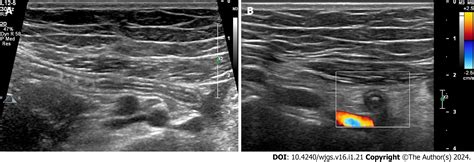

When patients present with abdominal pain—particularly in the lower right quadrant—medical professionals must quickly determine if the appendix is inflamed, a condition known as appendicitis. The primary diagnostic tool used in this process is imaging (ultrasound, CT scan, or MRI). By measuring the normal appendix size against current imaging, radiologists can identify inflammation, as an inflamed appendix will almost always appear enlarged due to swelling and fluid accumulation.

First, the imaging modality plays a significant role. CT scans are generally considered the gold standard for visualizing the appendix because they provide high-resolution, cross-sectional views. Ultrasounds are often used, especially in children or pregnant individuals to avoid radiation, but they can be limited by bowel gas or the patient's body habitus, making it harder to obtain an accurate measurement of the normal appendix size.

Furthermore, the physiological state of the appendix matters. If the appendix is not fully distended or if it is collapsed, it may measure differently. However, an inflamed appendix is typically filled with fluid, causing it to become rigid and distended, which actually makes it easier to measure compared to a normal, collapsed, or gas-filled appendix that may be difficult to visualize entirely.